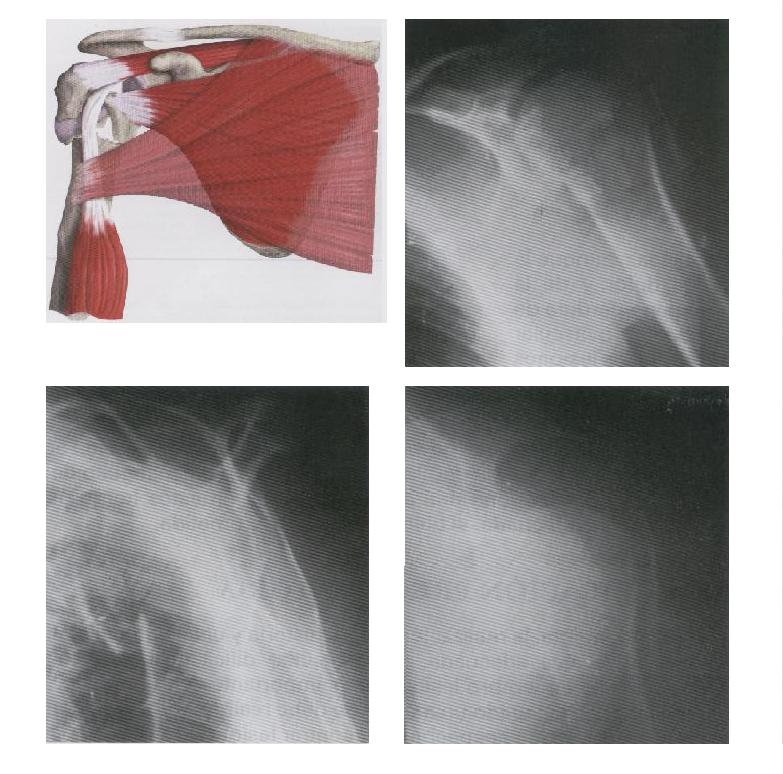

PACIENTE CON ENFERMEDAD DEGENERATIVA, DOLOR Y RESTRICCION DEL MOVIMIENTO

EL MISMO PACIENTE, DESPUES DE LA COLOCACION DE UNA PROTESIS TOTAL DE HOMBRO

DIAGRAMA DE UNA ARTROSCROPIA DEL HOMBRO

LIMPIEZA ARTICULAR POR ENFERMEDAD DEGENERATIVA DEL HOMBRO

FRACTURA DE 4 FRAGMENTOS DEL HOMBRO